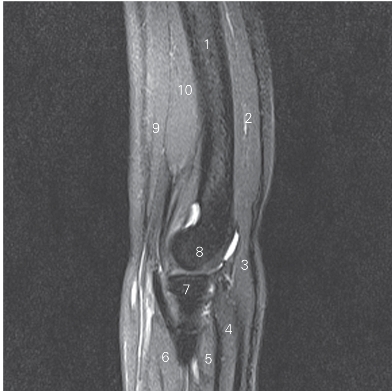

图4-34 经肘关节的矢状断层MR T2WI FS

1 肱骨体 body of humerus 2 肱三头肌 triceps brachii

3 肘肌 anconeus 4 尺侧腕伸肌 extensor carpi ulnaris

5 旋后肌 supinator 6 旋后肌 supinator

7 桡骨头 head of radius 8 肱骨小头 capitulum of humerus

9 肱二头肌 biceps brachii 10 肱肌 brachialis